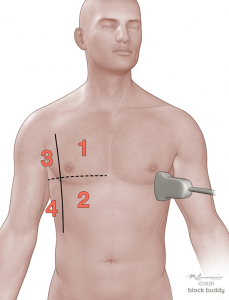

4. Positioning and Scanning

- Scanning can be performed with the patient in a supine, lateral or sitting position.

- In the critically ill patient, perform the scan with the patient supine and modified lateral position.

- When evaluating for a pneumothorax, perform the scan with the patient in the supine or semi-recumbent position.

- Use the anterior axillary (AAL) and posterior axillary (PAL) lines to divide each hemithorax into an anterior, lateral, and posterior zone.

- Further divide each zone into a superior and inferior region by drawing an imaginary horizontal line.

- This will create 6 zones over each hemithorax.

- Initially place the transducer in the long axis over zone 1.

- Reposition the transducer over each subsequent zone to complete the evaluation.